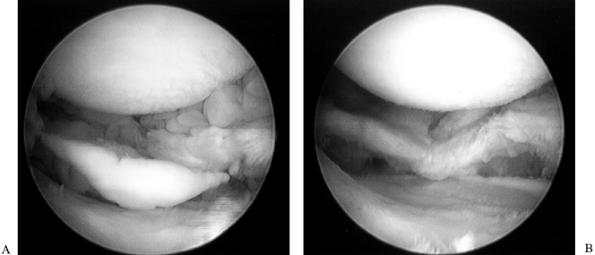

Expose the medial and lateral compartments in the routine manner (Fig. 84.28F). Excise the parameniscal synovium with the smaller synovial resectors (Fig. 84.29; see also COLOR FIG. 84.29).

Figure 84.29. Arthroscopic view of the lateral compartment (A) presynovectomy and (B) postsynovectomy. -